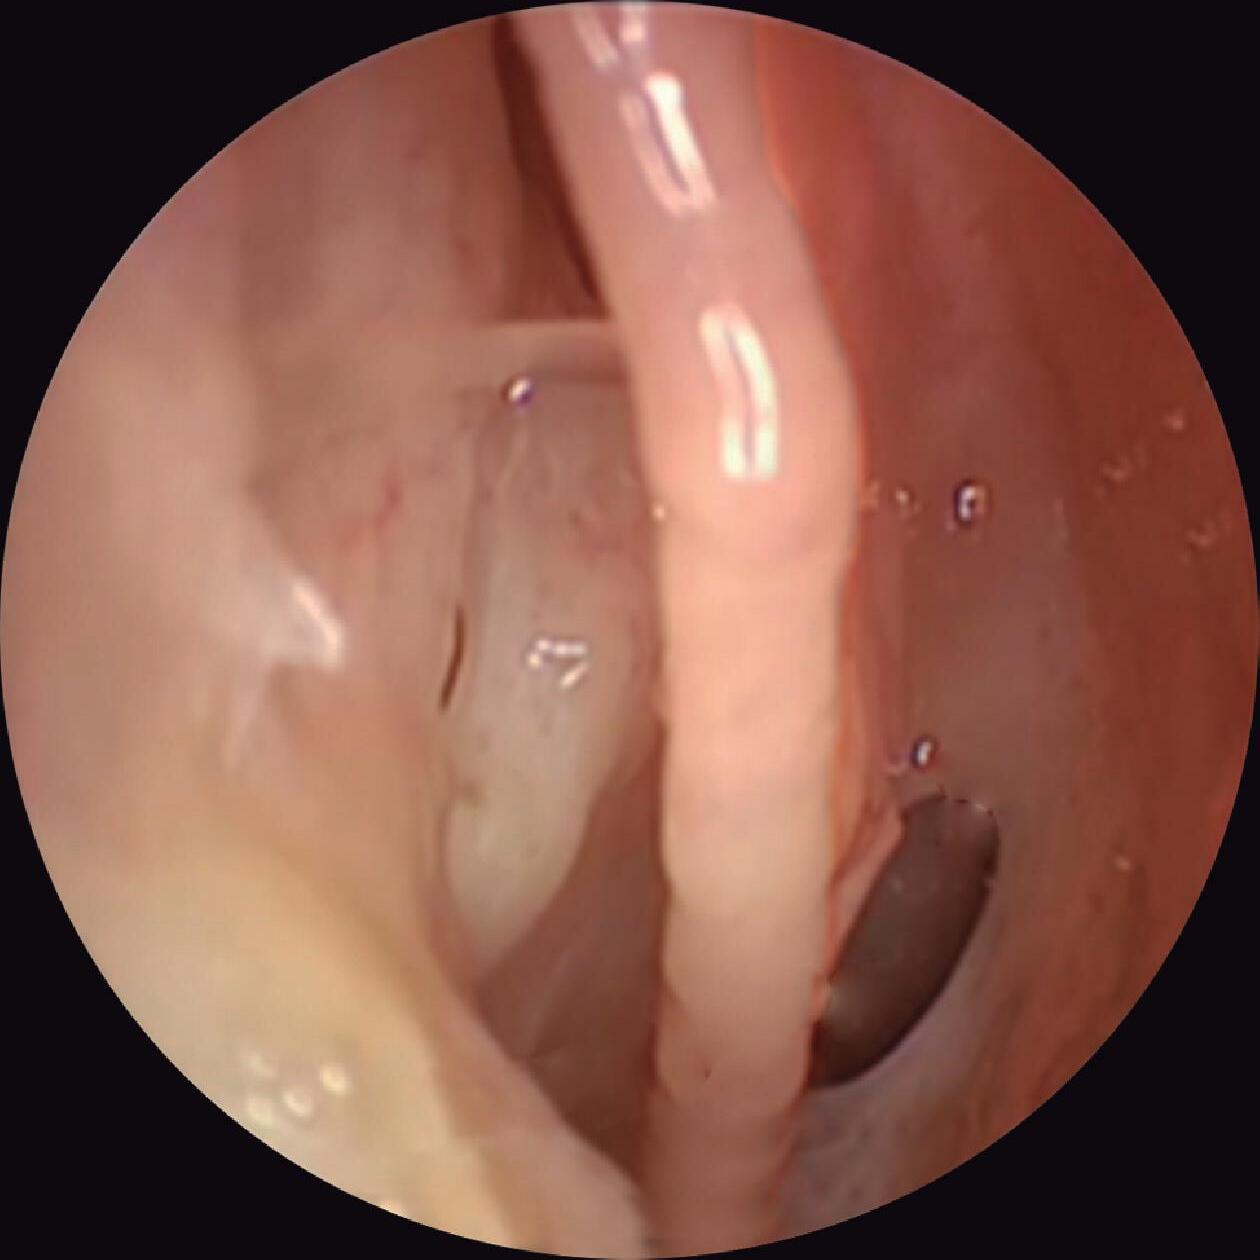

Fig. 1-24. Visão endoscópica do óstio esfenoidal direito – observar posição medial à concha superior; (1) septo, (2) óstio esfenoidal, (3) concha superior, (4) meato superior.